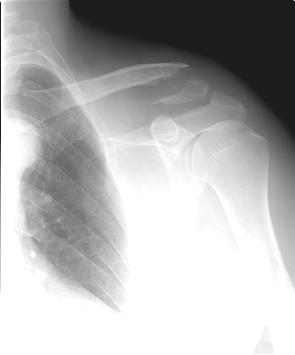

A 44 year old male 220 lb, but lean, body builder was riding his bicycle at about 30 km/hr and fell off onto his left shoulder. He is right hand dominant. He has an abrasion 3 cm posterior to the acromioclavicular joint. His left shoulder is anterior and caudad relative to the right shoulder. He is neurovasculary intact.

Radiographs show a displaced lateral 1/3 clavicle fracture (Neer type II). There is an inferior butterfly fragment that the conoid and trapizoid ligament most likely attach to.